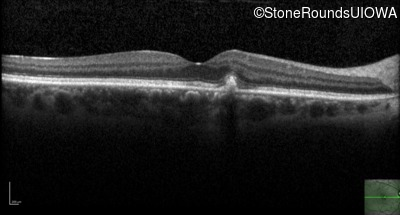

Optical Coherence Tomography - Right - 20/20 +1 sc

Exemplar / OCT Stack

Optical Coherence Tomography - Left - 20/25 +1 sc